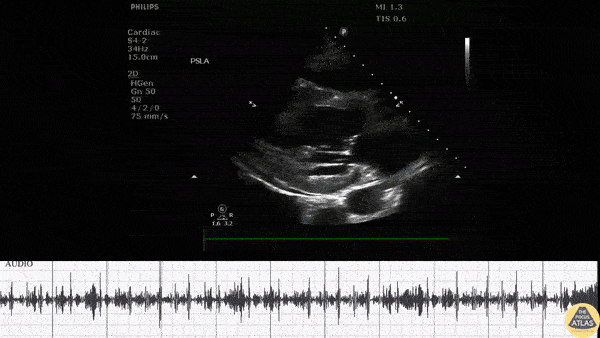

PLAX view in a patient who presented to the ED after missing several scheduled dialysis sessions reveals a small pericardial effusion with a pericardial friction rub on exam. Image courtesy of Robert Jones DO, FACEP @RJonesSonoEM Director, Emergency Ultrasound; MetroHealth Medical Center; Professor, Case Western Reserve Medical School, Cleveland, OH View his original post here